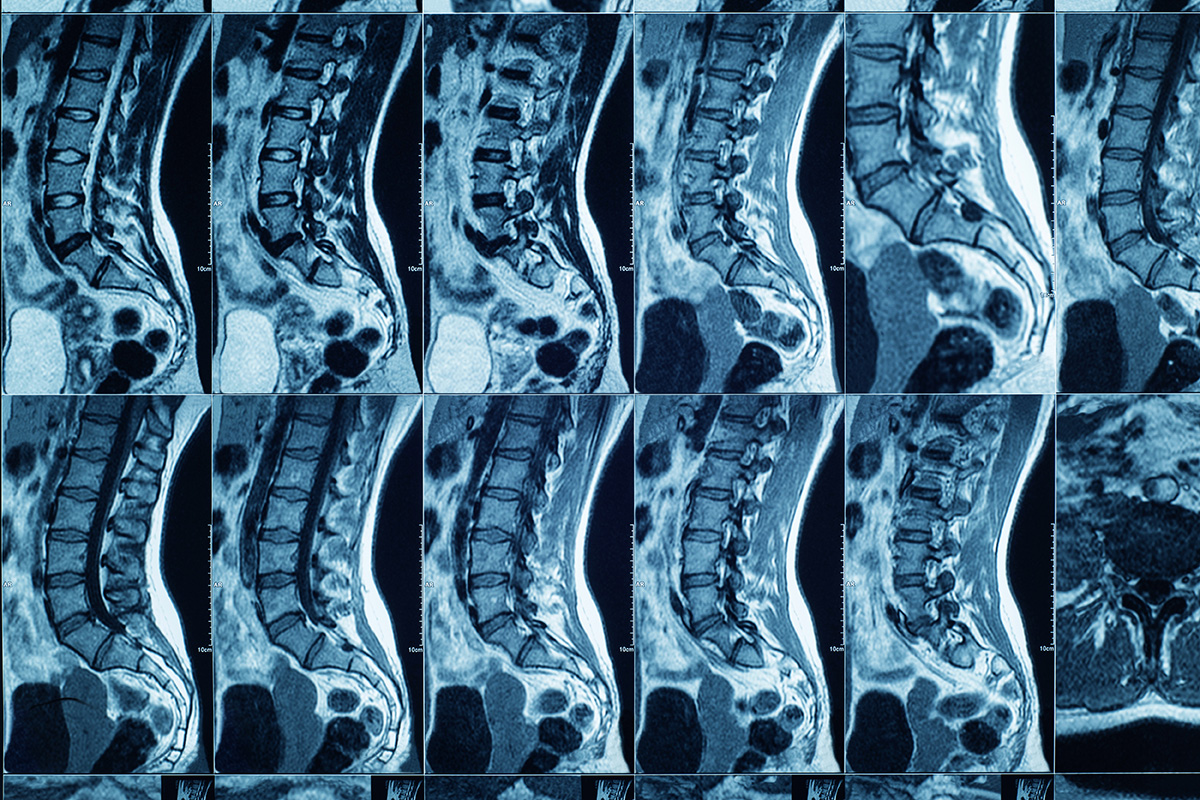

I percorsi diagnostici prevedono l'utilizzo di strumenti quali risonanza magnetica (RM), elettroencefalogramma (EEG), elettromiografia (EMG), potenziali evocati, doppler transcranico e test neuropsicologici specifici. Le terapie comprendono trattamenti farmacologici personalizzati, fisioterapia neuromotoria, terapia cognitiva e comportamentale, stimolazione magnetica transcranica (TMS) e infiltrazioni con tossina botulinica per specifiche condizioni neurologiche. Sono previsti percorsi educativi e di supporto psicologico per pazienti e caregiver.